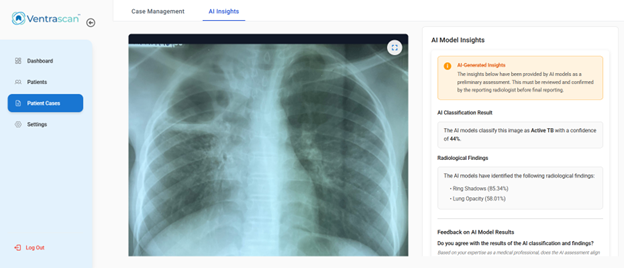

Designed to support—not replace—clinicians

Delivers explainable insights such as visual markers and confidence scores to aid clinical judgment, while final diagnostic decisions remain with qualified healthcare professionals.

- Support clinical decision-making with explainable outputs